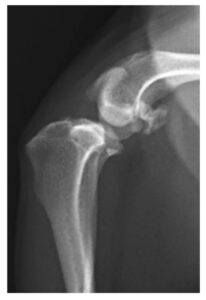

症例1. TPLOを実施した症例(7歳、ビーグル、9 kg)

| 治療前(側方像) | 治療後(側方像) | 治療前(前後像) | 治療後(前後像) |